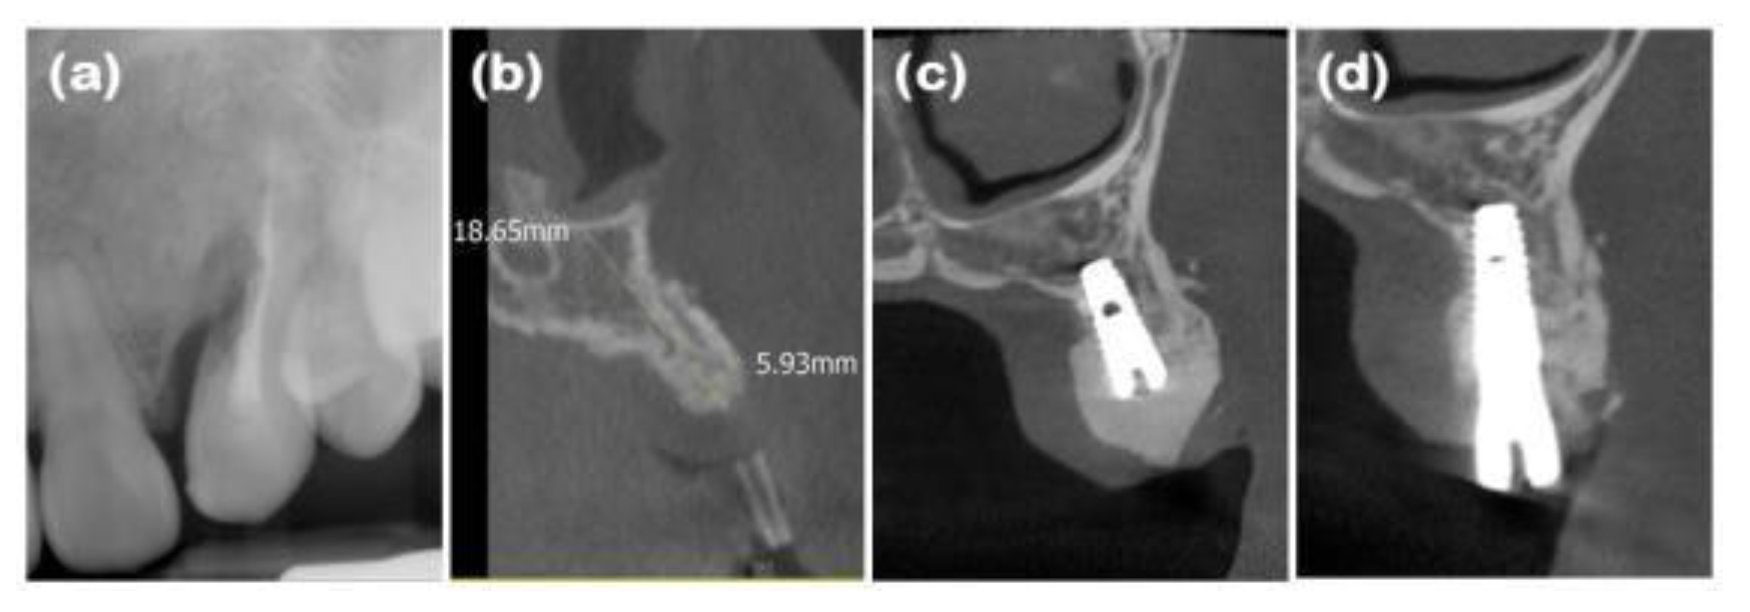

Figure 2. Radiographs of case 1. (a) Periapical radiograph showing external root resorption of the maxillary left canine. (b) Cone-beam computed tomography (CBCT) image displaying the augmented site after healing. Alveolar ridge width was measured at approximately 5.93mm, which is sufficient for the placement of a standard diameter implant. (c) Post-implant placement with guided bone regeneration, demonstrating bone material surrounding the implant fixture. (d) Following the second implant surgery, the contour of the bone graft was well maintained.

After performing full-mouth scaling, #23 was extracted and ARP was performed a month later. A horizontal incision was made on the palatal side, and a full-thickness flap, including the interdental papilla, was elevated buccally. The periapical cystic lesion was removed, revealing extensive horizontal and vertical bone defects as well as buccal bone plate loss (Figure 1b). A synthetic bone graft material mixed with collagen (Osteon 3 collagen® (biphasic calcium phosphate with collagen), Genoss Co. Ltd., Suwon, Korea) was inserted into the extraction socket, and to fully cover the alveolar crest, a resorbable collagen membrane with soft-type stiffness (Collagen membrane 2®, Genoss Co. Ltd.) was applied. To reconstruct the buccal bone wall, a resorbable collagen membrane with medium-type stiffness (Collagen membrane P®, Genoss Co. Ltd.) was placed over the buccal side of the socket. Due to the extensive buccal bone loss, a soft tissue graft between the membrane and the flap was necessary to compensate for soft tissue collapse and delayed healing. A xenogenic collagen matrix (Collagen graft 2®, Genoss Co., Ltd.) was inserted buccally and slightly on the crestal area (Figure 1c,d). The area was sutured without tension using 6-0 Vicryl (Ethicon, INC., a Johnson & Johnson company, Somerville, USA) and 5-0 Black nylon (AILEE Co., Ltd., Busan, Korea), and intentional secondary healing (open healing) was induced. Upon suture removal 10 days later, secondary healing was observed, with no significant findings other than partial exposure of the bone graft material on the buccal side. The secondary healing area was continuously monitored. After confirming the epithelialization of the soft tissue and the complete regeneration of the interdental papilla between the adjacent teeth, the first implant surgery was performed 9 months after the alveolar ridge augmentation. Prior to implant placement, the width and height of the remaining alveolar ridge were observed to be in good condition (Figure 1e and Figure 2b). A full-thickness flap was elevated, revealing a sufficiently augmented alveolar bone with a width of approximately 6 mm bucco-palatally. The implant was placed in an ideal position (Superline Φ3.5×10 mm, Dentium, Seoul, Korea), and to compensate for the loss of bone graft material due to drilling, additional guided bone regeneration (GBR; Osteon 3 collagen® and Collagen membrane P®, Genoss Co., Ltd.) was performed on the palatal side (Figures 1f and 2c). Five months after the first implant surgery, the second implant surgery was carried out (Figure 1g and 2d). Seven months after the first implant surgery, a customized abutment and veneered zirconia were placed. The interdental papilla between #22 and #23 was regenerated, and 4 mm of buccal keratinized mucosa was stably observed (Figure 1h).

In this study, ARP was performed with flapped surgery in patients who required horizontal and vertical bone augmentation due to the absence of residual bone. A collagen matrix was used to compensate for ridge contraction and to increase the keratinized mucosa around the implants. In case 1, the buccal bone plate at site #23 had been resorbed, resulting in a narrow alveolar ridge width in the bucco-palatal direction, which was insufficient for implant placement. To augment the buccal bone, xenogenic bone graft material, two-types of resorbable collagen membranes, and a xenogenic collagen matrix were applied, sequentially. At the time of implant placement, a ridge width of approximately 5.93mm was observed bucco-palatally, and continuous, intact soft tissue regeneration, including preservation of the interdental papilla, was achieved. In case 2, the bone wall at extraction site #16 had resorbed, necessitating both bone and soft tissue augmentation for predictable implant placement. Periodontal flap surgery was also performed on the adjacent teeth, resulting in a wider incision. A xenogenic collagen matrix was applied to promote adequate soft tissue regeneration. At the time of implant placement, ridge widths of approximately 8.66 and 8.90mm were observed bucco-palatally at sites #16 and #17, respectively, along with a continuous soft tissue contour. In case 3, following the extraction of teeth #31, #32, #41, and #42, the buccal bone plate had been resorbed. After broad ridge augmentation, a xenogenic collagen matrix was applied to aid in soft tissue regeneration and preservation of the interdental papilla. At the time of implant placement, ridge widths of approximately 4.92 and 4.33mm were observed bucco-palatally at sites #32 and #42, respectively, along with continuous soft tissue contour. Upon completion of the implant prosthetics, a natural appearance of the interdental papilla was observed continuously. In case 4, horizontal and vertical alveolar bone defects were observed in explanted sites #46i and #47i, along with a shallow buccal vestibule and insufficient keratinized mucosa. A xenogenic collagen matrix was applied to the buccal and crestal side to ensure sufficient alveolar bone augmentation and keratinized mucosa for implant placement, and the modified Edlan–Mejchar technique was used to deepen the buccal vestibule. At the time of implant placement, ridge widths of approximately 7.90 and 5.58mm were observed bucco-palatally at sites #45 and #47, respectively, while maintaining the natural soft tissue appearance and deepened vestibule. In respect of the anterior teeth in case 1 and case 3, the PES/WES values ​​were measured as 7~8 points, confirming that although the periodontal defects were severe, good esthetic results could be obtained. In the CBCT cross-sectional view and clinical examination of all cases, the alveolar bone width was appropriate for implant placement of narrow diameter or more in the anterior region and regular diameter or more in the posterior region. In addition, the width of the buccal keratinized mucosa was confirmed to be consistently well-maintained at 2 mm or more in all cases. Although there are many opposing views, it is important to secure the presence of keratinized mucosa with more than a 2mm width around the implant for the health and maintenance of the implant [19].